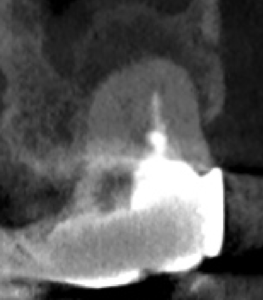

またMB2の多くはMB1と合流するという臨床的事実から形成済みのMB1に当該Gutta Percha Pointを挿入しMB2にFileを入れてグリグリとやってみた。

すると…

13.5mmの地点に傷がついていることがわかる。

ここが合流地点だろう。

これで以下のように作業を行った。

MB2は狭窄根管だがMB1と合流しているので13.5mmとして形成した。